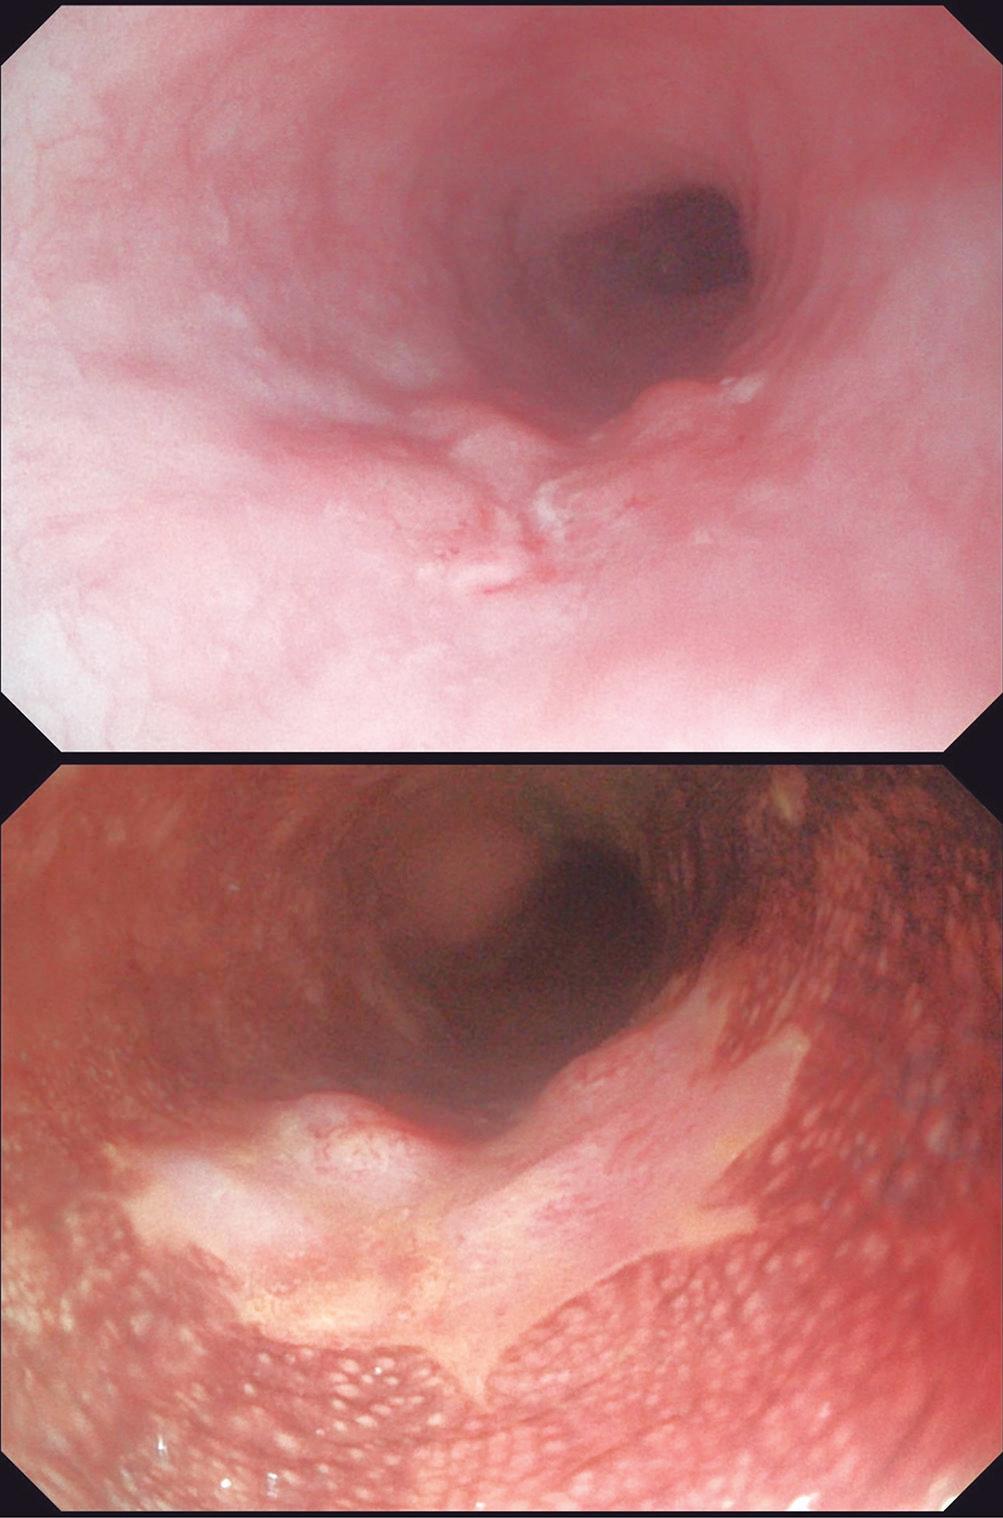

Evaluación de un paciente con dolor epigástrico y hallazgos sincrónicos infrecuentes

Roy López Grove, Daniela Soloaga, Juan Carlos Spina

Roy López Grove, Daniela Soloaga, Juan Carlos Spina 398